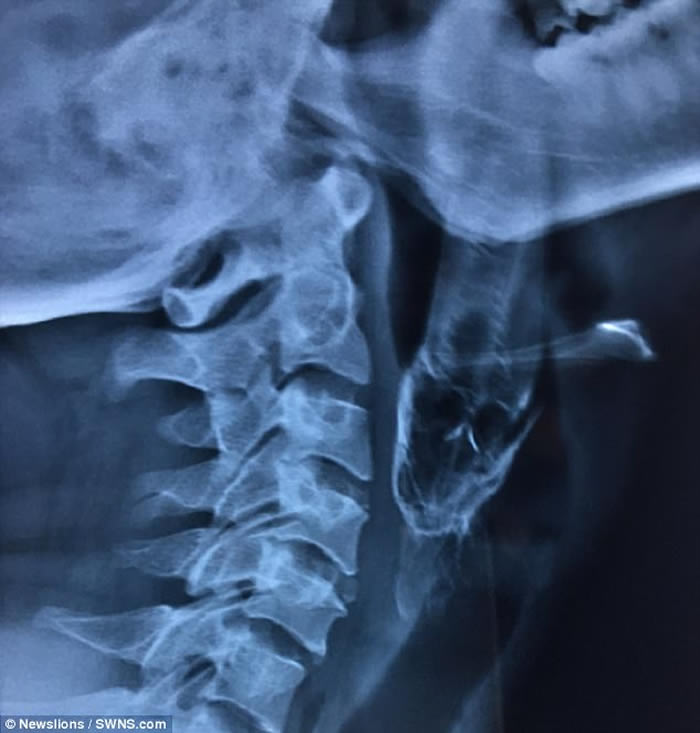

(神秘的地球uux.cn报道)印度一名30岁男子早前意外将一条4吋长的活鱼吞下,导致不能呼吸及说话,需紧急送往医院。惟医生起初未能取出,需转送另一医院,医生最后成功用钳将鱼取出。

男事主达什(Santosh Dash)当日在池塘徒手捉了一条攀鲈,后者竟飞进他的口中,卡在喉咙,致几乎窒息。达什被送院后,医生设法取出活鱼但不果,需转送距达什村庄200米外的医院。

医生指,达什入院时,可从其口腔中望到鱼尾,随即送入急症室接受局部麻醉,再撑开其口用钳把鱼拉出。医生表示,达什的喉咙遭攀鲈割伤,需以鼻胃管喂食10天,现时已出院。